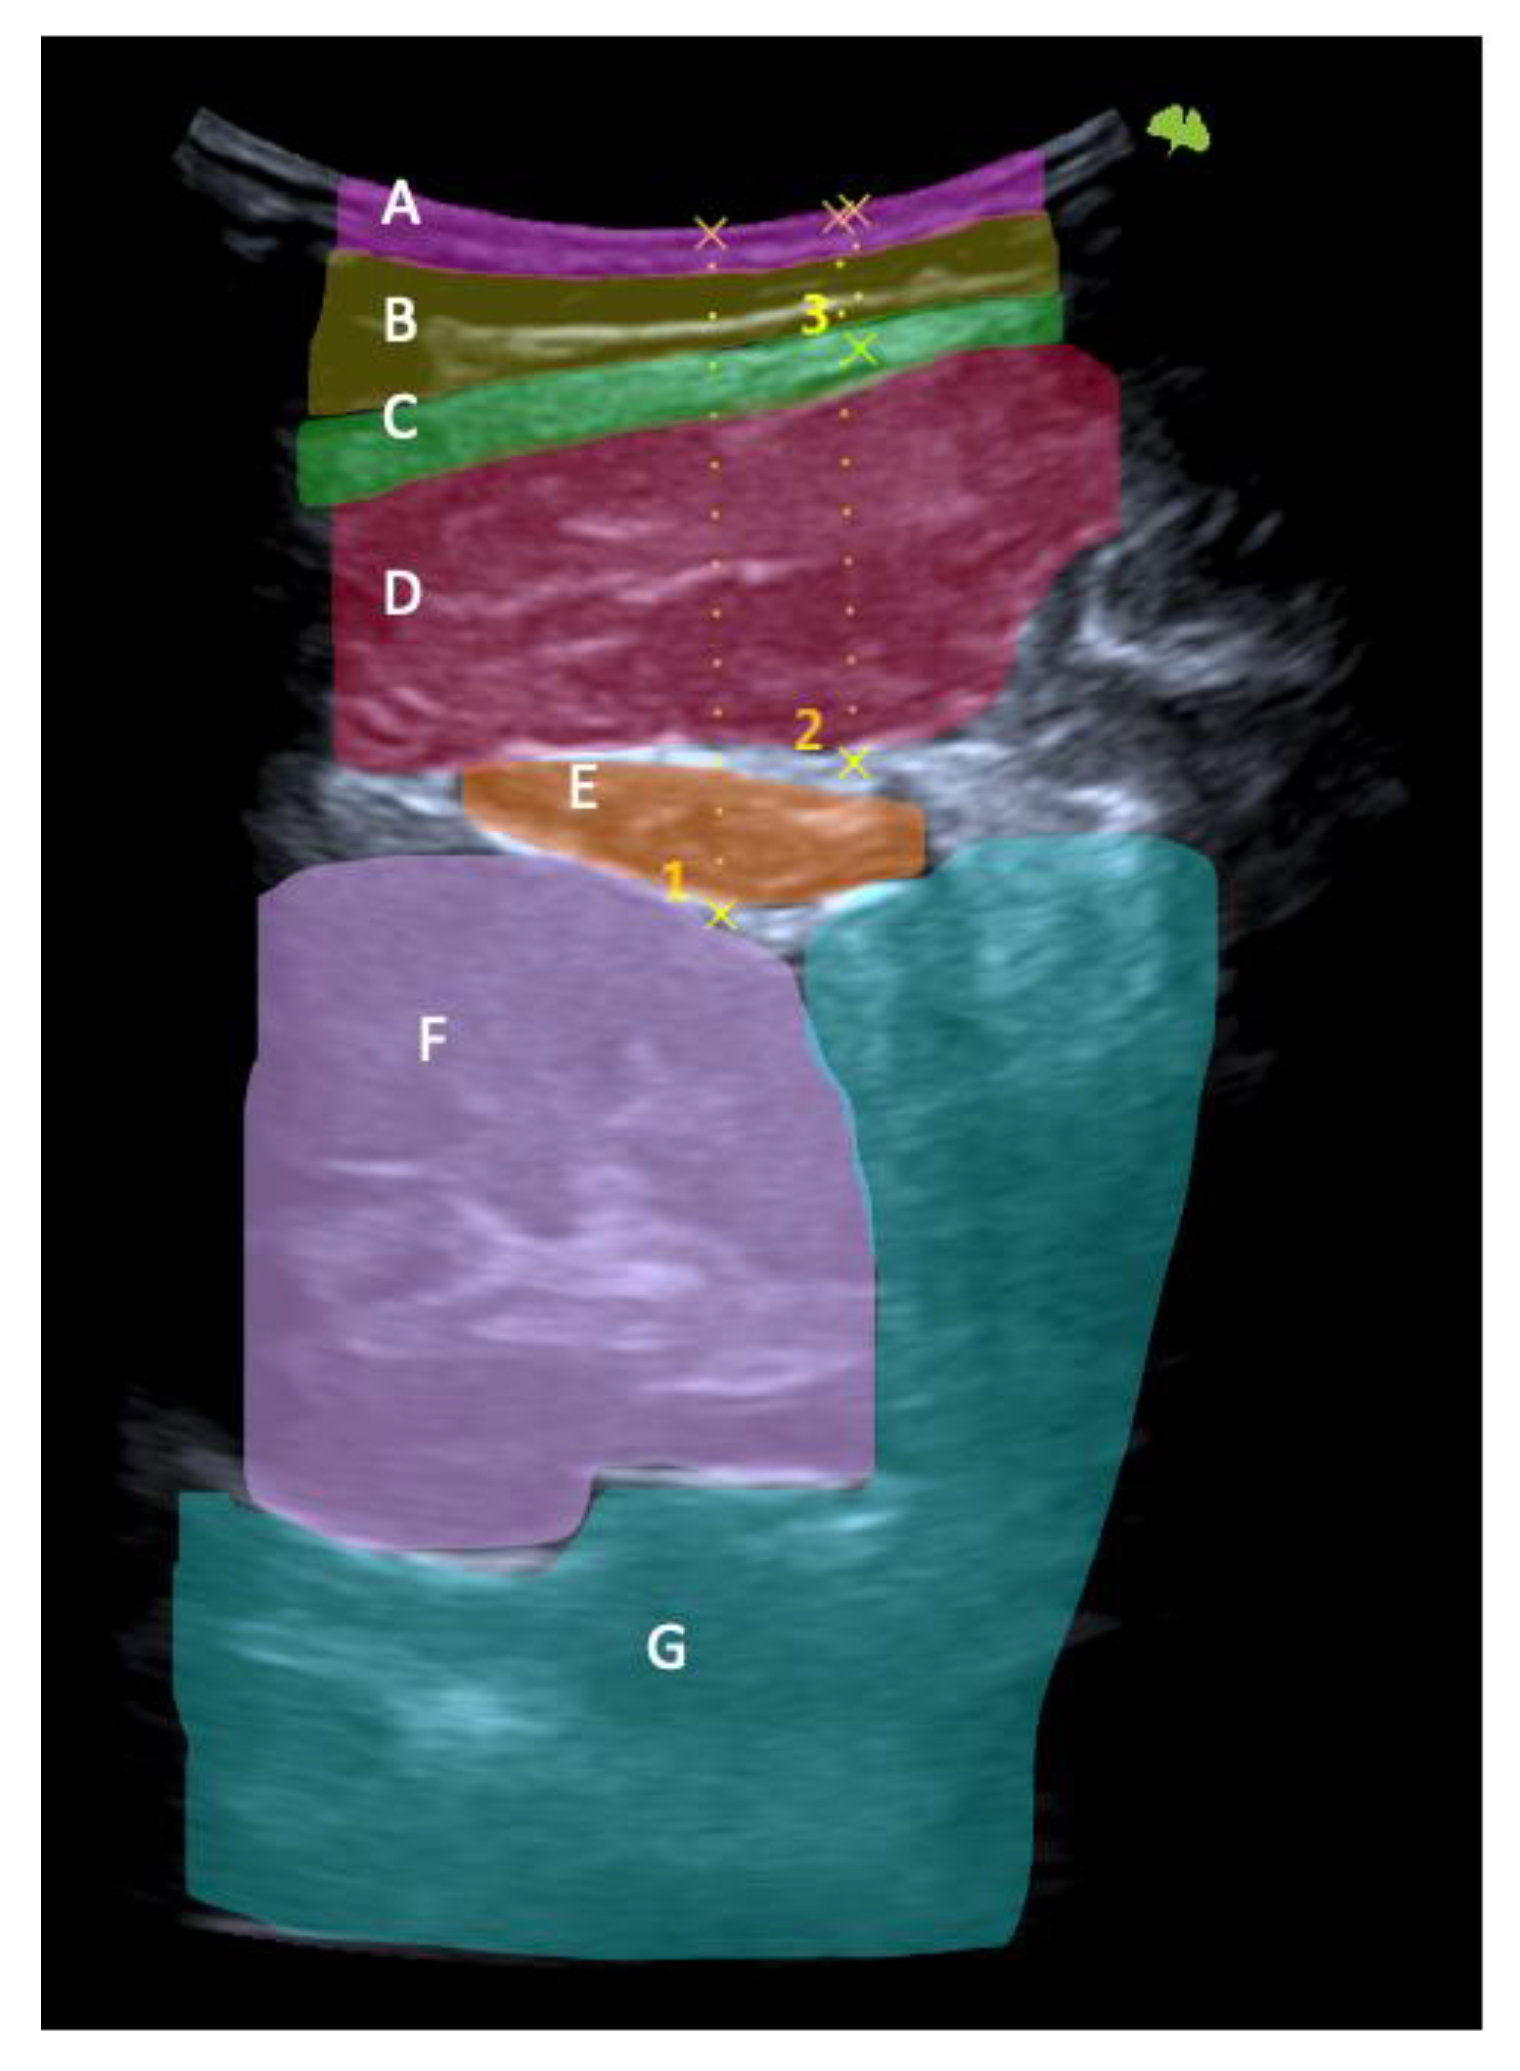

First, the last lumbar vertebra and the first sacral vertebra were located, and from there, the spinous processes of L4 and L2 were marked and assessed using ultrasonography. At the level of L2, the spinous process is located in the short axis, and the probe was moved to the right or left lateral side depending on randomization. We visualized the skin and the fatty tissue, we left the longissimus muscle towards the medial side, and we placed the iliocostalis lumborum muscle in the long axis, as well as the quadratus lumborum and the kidney, in the center of the screen. We asked the subjects to breathe in to see how the kidney descended and became more visible. When in maximum inspiration, we froze the image to make the following measurements: skin-upper edge of the iliocostalis lumborum muscle, skin-lower edge of the iliocostalis lumborum muscle, and skin-kidney. Then, a different researcher placed two fingers exerting pressure, as if it were the “tissue depression prior to performing the DP”. More ultrasound gel was placed between the fingers, and the sonographer placed the probe again in the short axis. An inspiration was requested to freeze the image and perform the same measurements mentioned above. At L4 level, the same protocol was followed with the difference in that, instead of performing the last skin-kidney measurement, the skin-peritoneum measurement was performed. The measurements were made on the right and left sides and with and without compression (Figure 3, Figure 4 and Figure 5).

Figure 4. Ultrasonography image. Short-axis view: skin (A), fat (B), thoracolumbar fascia (C), iliocostalis muscle (D), quadratus lumborum muscle (E), kidney (F), and peritoneum (G). Skin-kidney (1), skin-iliocostalis lumborum bottom edge (2), and skin-iliocostalis lumborum top edge (3).